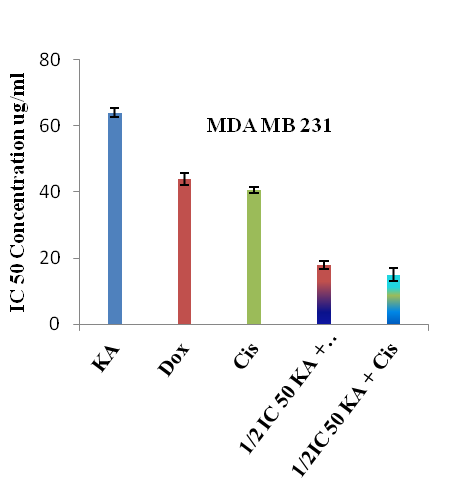

Combination effect of kaempferol and chemotherapeutic drugs on cell growth

The combination effect of kaempferol with doxorubicin or cisplatin in the HCT-15 and MDA MB 231 cell lines has been represented in CI and the results are summarised. The data was examined using median effect analysis to determine the type of interactions which occurred, i.e., antagonism (CI>1), additivity (CI=1) or synergism (CI<1) (table 3).

The CI values for HCT-15 and MDA MB 231, when treated with kaempferol in combination with doxorubicin/cisplatin, were 0.45 and 0.65, 0.55 and 0.65 respectively, where CI<1 means synergism, CI=1 means additive effects and CI>1 means antagonism. In all combination treatments, the concentrations of doxorubicin and cisplatin necessary to inhibit 50% of cancer cells (IC50) were reduced by 5 and 2.5 fold for HCT-15 and 2.4 and 2.6 fold for MDA MB 231 respectively. To assess the effect of kaempferol and doxorubicin or cisplatin on HCT-15 and MDA MB 231 cell growth, cells in the exponential growth phase were treated with different doses of kaempferol (5, 10, 25, 50, 100 and 150 µg/ml), doxorubicin (5, 10, 25 and 50 µg/ml) and cisplatin (5, 10, 25 and 50 µg/ml) for 24 h. At the end of the treatment, the determination of % cell death showed that these agents inhibited cell growth in a dose-dependent manner. On the basis of these results, experiments were performed on both the cell lines (for 24 h) by combining kaempferol at 30 µg/ml (1/4 IC50) with doxorubicin/cisplatin at 5, 10, 25 and 50 µg/ml for HCT-15 (fig. 5). The experiment was repeated for MDA MB 231 cells by considering the concentrations of kaempferol with doxorubicin/ cisplatin as 32 µg/ml (1/2 IC50) and 5, 10, 25 and 50 µg/ml respectively (fig. 6). At the end of the experiments, significant synergistic growth inhibition of both HCT-15 and MDA MB 231 was observed.

The increase in systemic toxicity and drug resistance are the major drawbacks of cancer chemotherapeutic agents are led to a new challenge in the field of cancer research. To overcome this problem, extensive research has been directed towards reducing systemic toxicity and increasing drug activity in cancer therapy [2]. In this regard, combination therapy has received more attention for the purpose of finding compounds with a known mechanism of action that could increase the therapeutic index of clinical anticancer drugs [17]. The above results indicate that the in vitro therapeutic effect of doxorubicin in terms of cell growth inhibition at the 49.6±0.5 µg/ml dose was achieved at its one-fifth concentrations (10.2±0.83 µg/ml) in combination with 30 µg/ml dose of kaempferol in HCT-15 cells whereas with cisplatin, cell growth inhibition at 25.4±2.9 µg/ml was achieved at its half concentration (10±1.34 µg/ml dose) in combination with 30 µg/ml dose of kaempferol.

However, phytochemical kaempferol and therapeutic drugs doxorubicin and cisplatin showed the cytotoxic effect on HCT-15 cells individually at 120±3.2 µg/ml, 49.6±0.5 µg/ml and 25.4±2.9 µg/ml respectively. Simultaneously, on MDA-MB 231 cell line, the in vitro therapeutic effect of doxorubicin and cisplatin was achieved at 44±1.8 µg/ml and 40.6±0.8 µg/ml was reduced to 18±1.22 µg/ml and 15±1.87 µg/ml in combination with 32 µg/ml dose of kaempferol.

Fig. 6: IC50 Concentrations of kaempferol, doxorubicin and cisplatin alone and in combination on human breast cancer cells (MDA-MB 231). KA-Kaempferol, Dox-Doxorubicin, Cis-Cisplatin, n=5